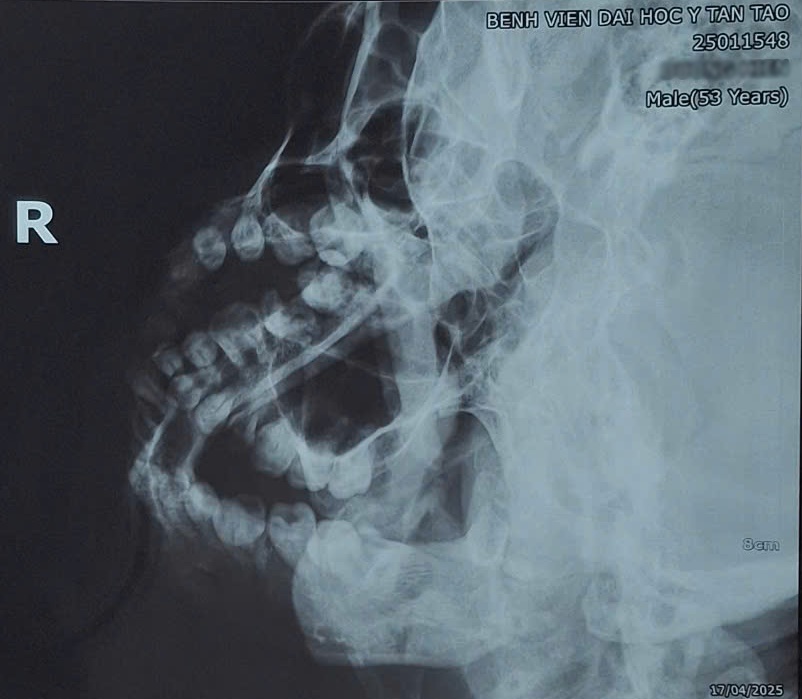

Qua thăm khám lâm sàng và chụp X-quang, các bác sĩ chẩn đoán bệnh nhân D.H bị trật chỏm xương hàm dưới bên phải ra khỏi hố khớp thái dương – hàm dưới.